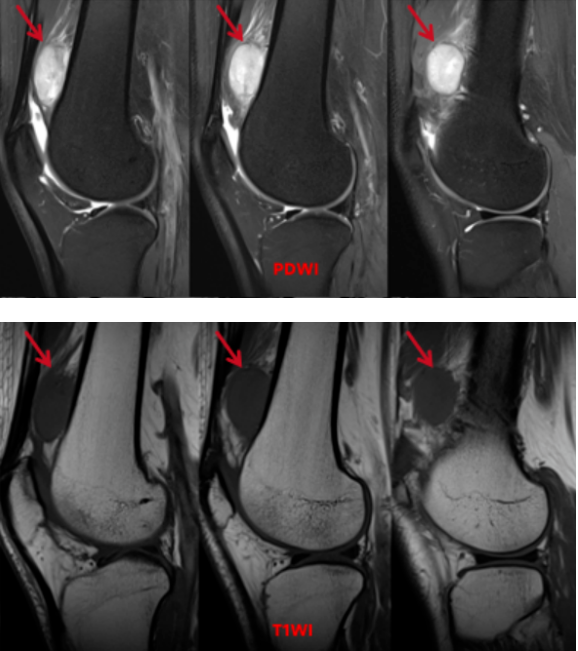

左膝关节MRI平扫:左股骨下段骨干前方软组织内(股中间肌与股外侧肌交界区)可见类圆形团块状稍长T1信号,PDWI呈稍混杂高信号,大小约15x32x37mm,边界清晰,其内信号欠均匀、可见点线状低信号,病灶边缘欠规整,邻近周围软组织见少许条片絮状片高信号,相应骨质未见破坏。

影像诊断:左股骨下段骨干前方占位,倾向于良性可能性大,筋膜来源肿瘤性病变-结节性筋膜炎可能,建议临床活检

多参数、多序列成像:MRI可以利用不同的扫描序列(如T1WI、T2WI、PDWI、脂肪抑制序列等),从多个“角度”反映组织的不同物理和生化特性。这有助于判断病变的 成分(如是否含水多、含脂肪、含纤维、含血)、边界、与周围重要结构(如血管、神经)的关系,从而为鉴别肿瘤的良恶性、推断其来源提供丰富信息。